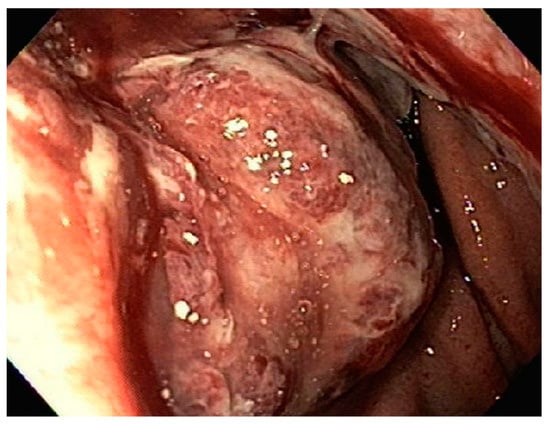

| 3 | F | 35 | Lung | Fundus | Fungating mass | Esophagus, mediastinum | Large-cell neuroendocrine carcinoma | Chemotherapy-carboplatin/ etoposide | Death 1 month after EGD diagnosis of metastasis |

| 4 | F | 73 | Kidney | Fundus and body | Multiple large friable masses | Liver and lungs | Clear cell renal carcinoma | Nephrectomy, chemotherapy, immunotherapy (Axitinib) | Death 10 days after EGD diagnosis of metastasis |